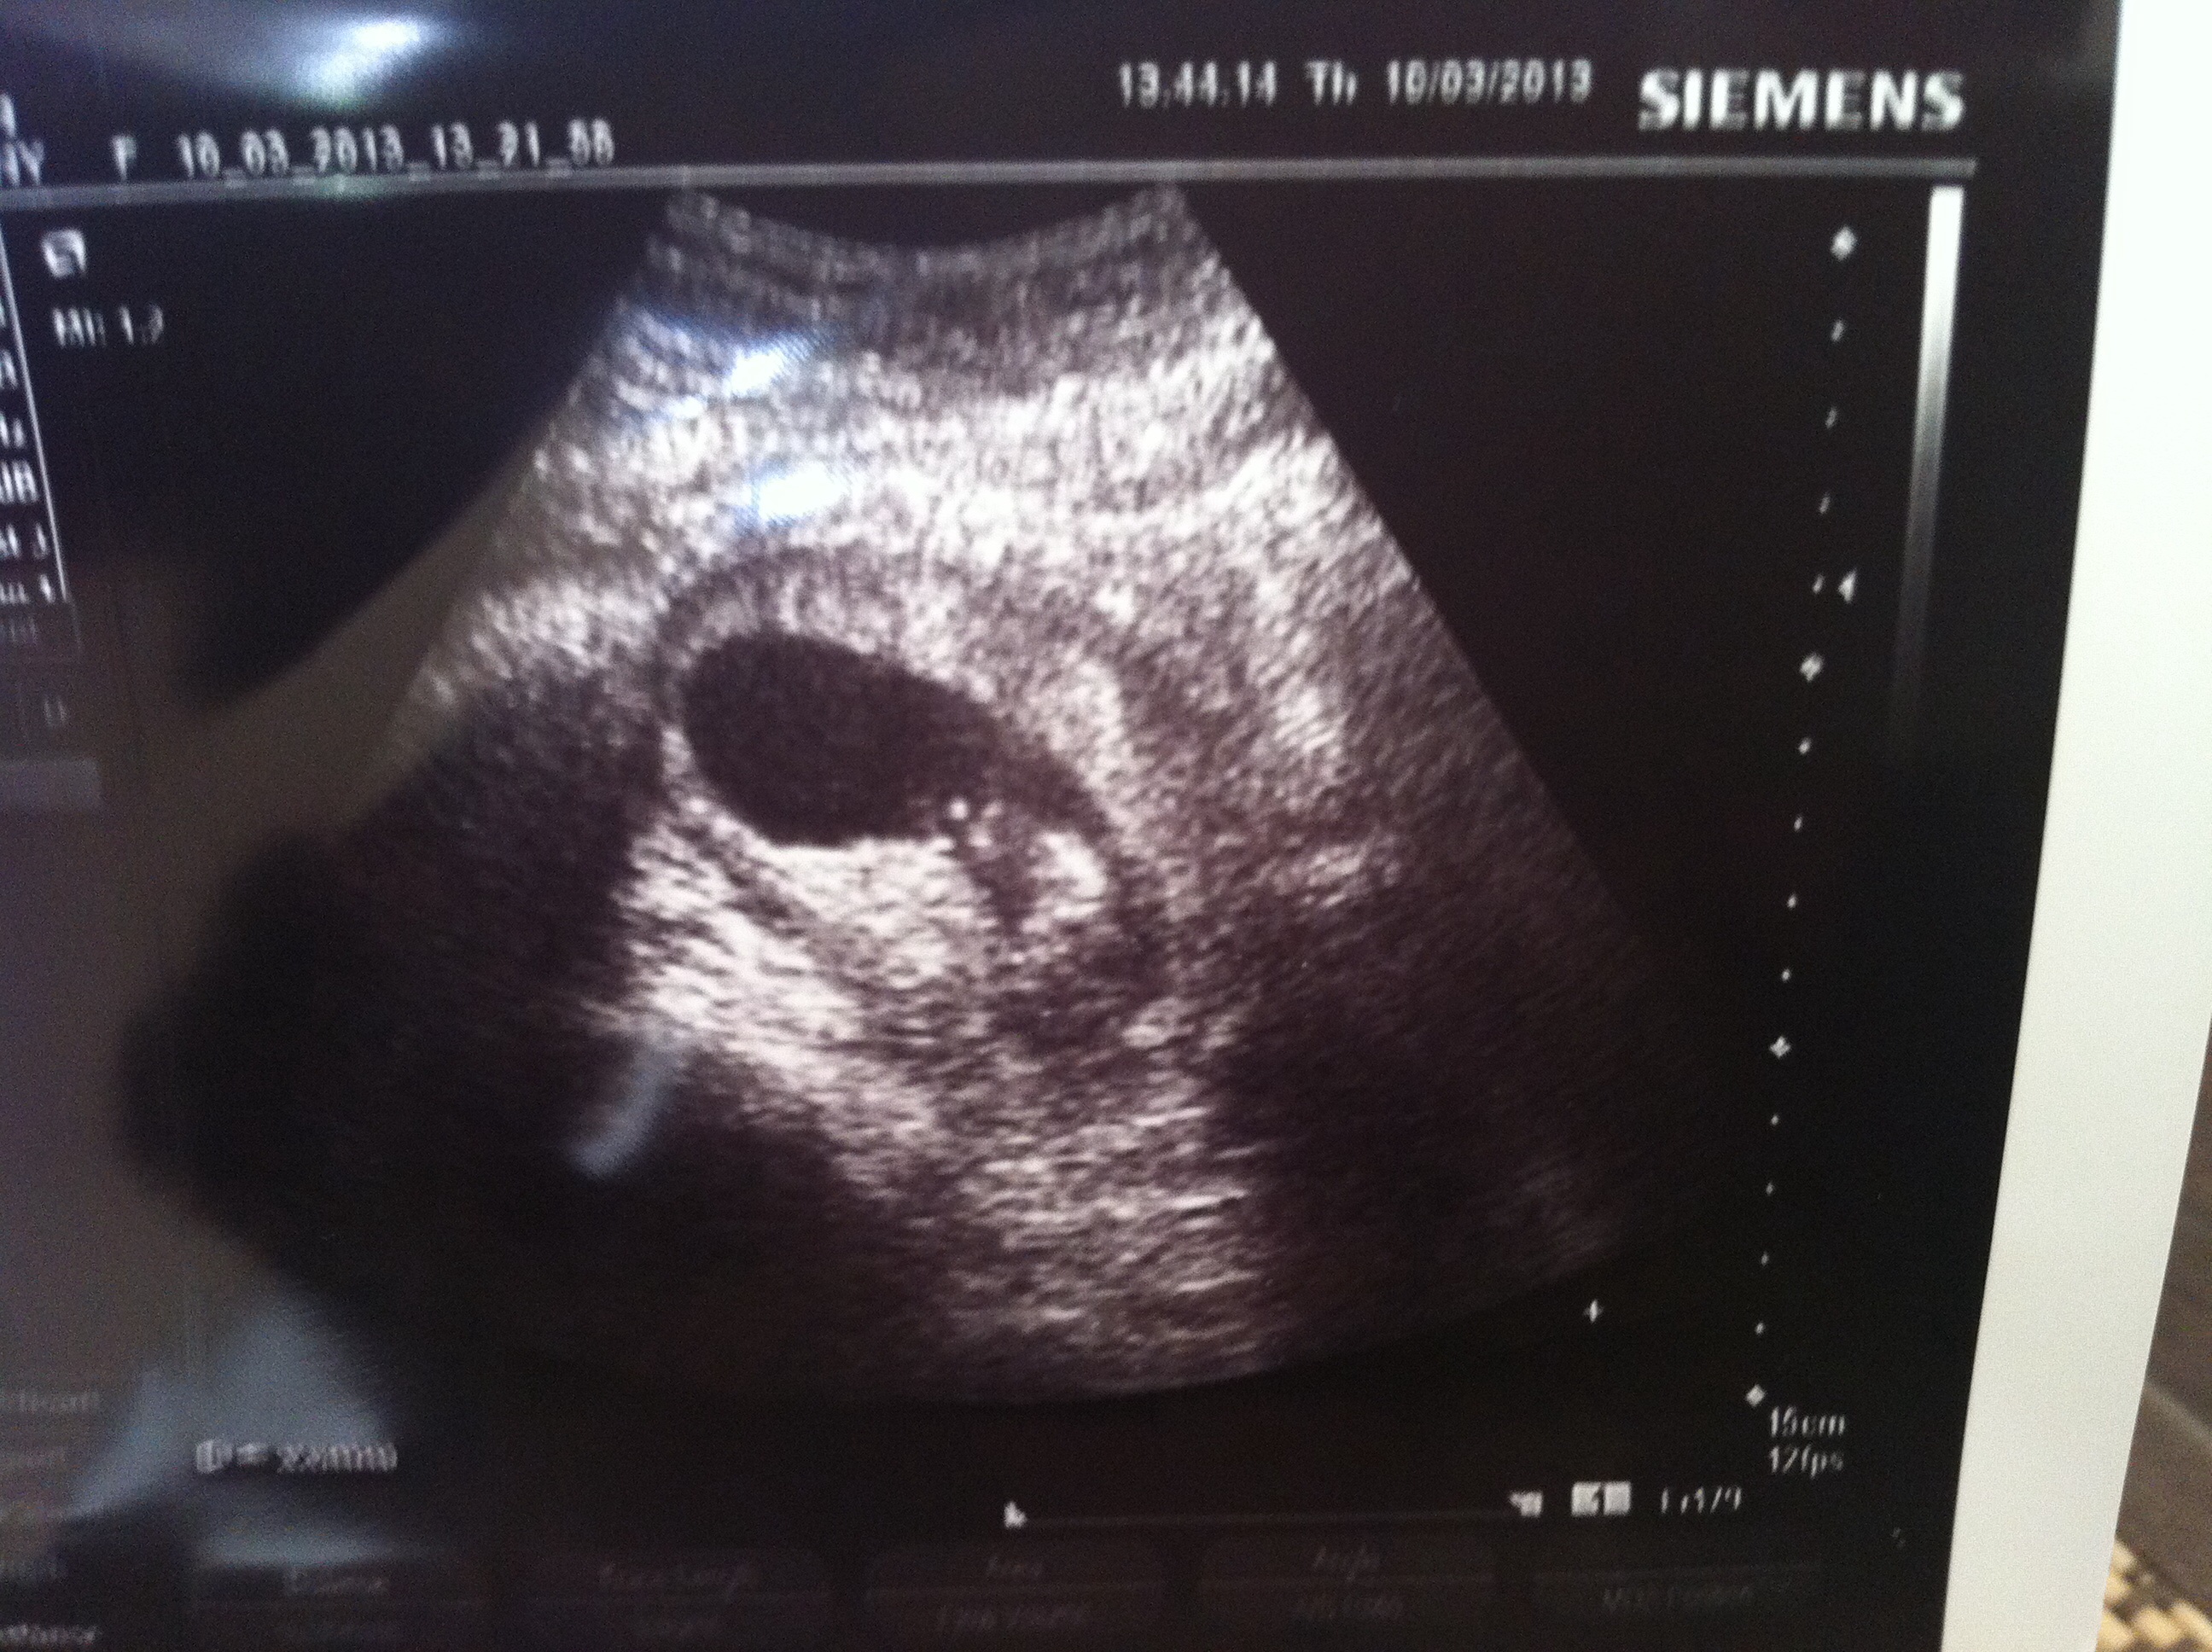

Went in yesterday an saw our little jelly bean. Heart rate is strong 168! Dr said I can have a cup of coffee a day to help my extreme fatigue so today is gonna be the first day having caffeine in MONTHS!!! I may be detailing my house! Haha

10 weeks 5 days...